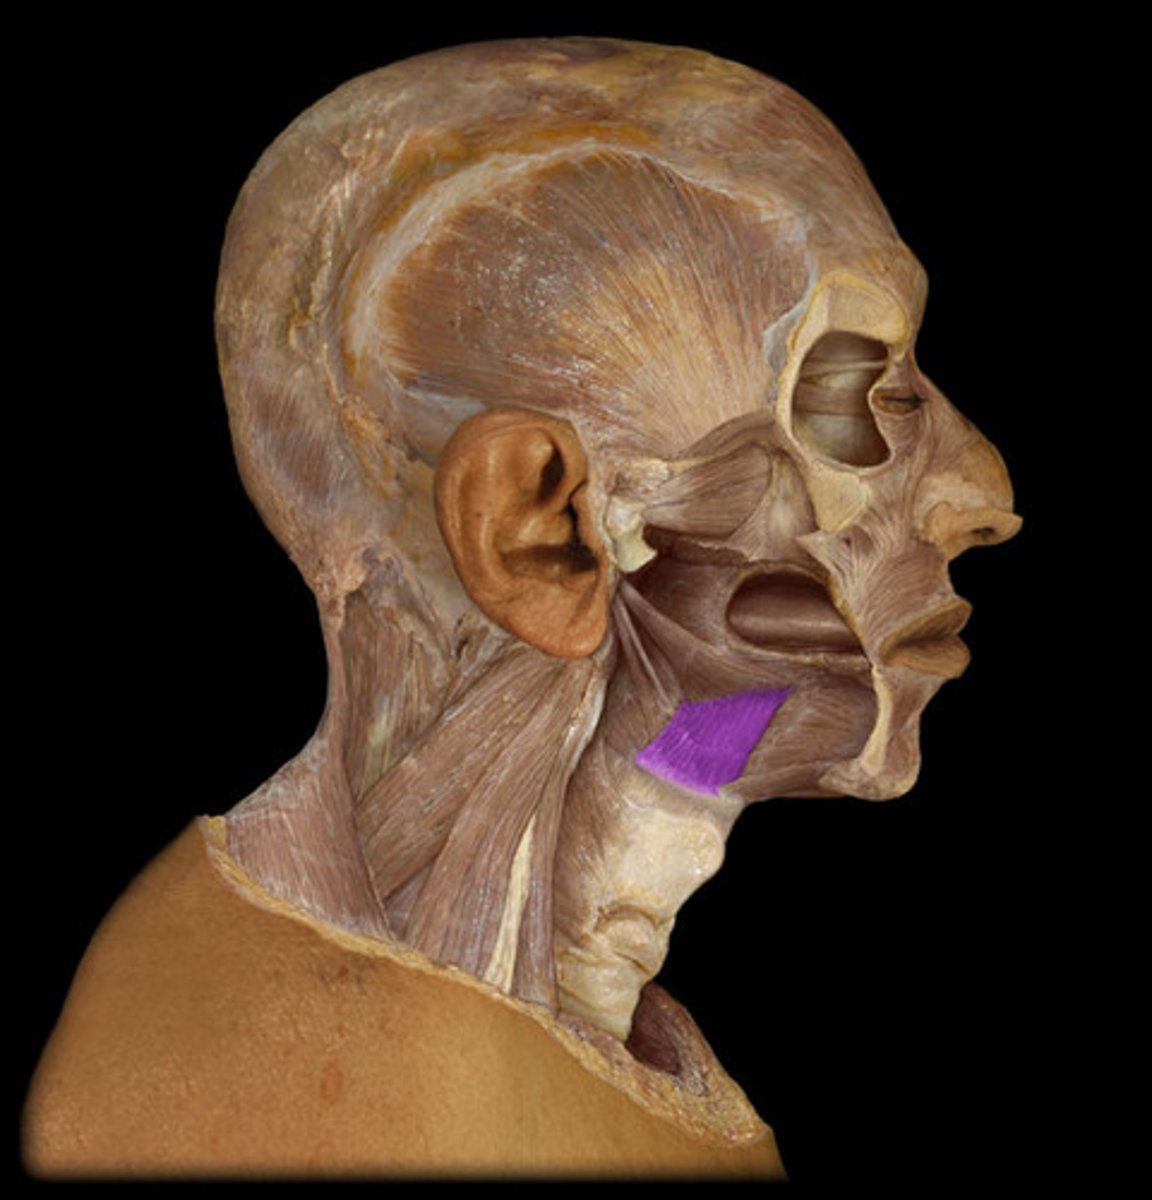

Platysma